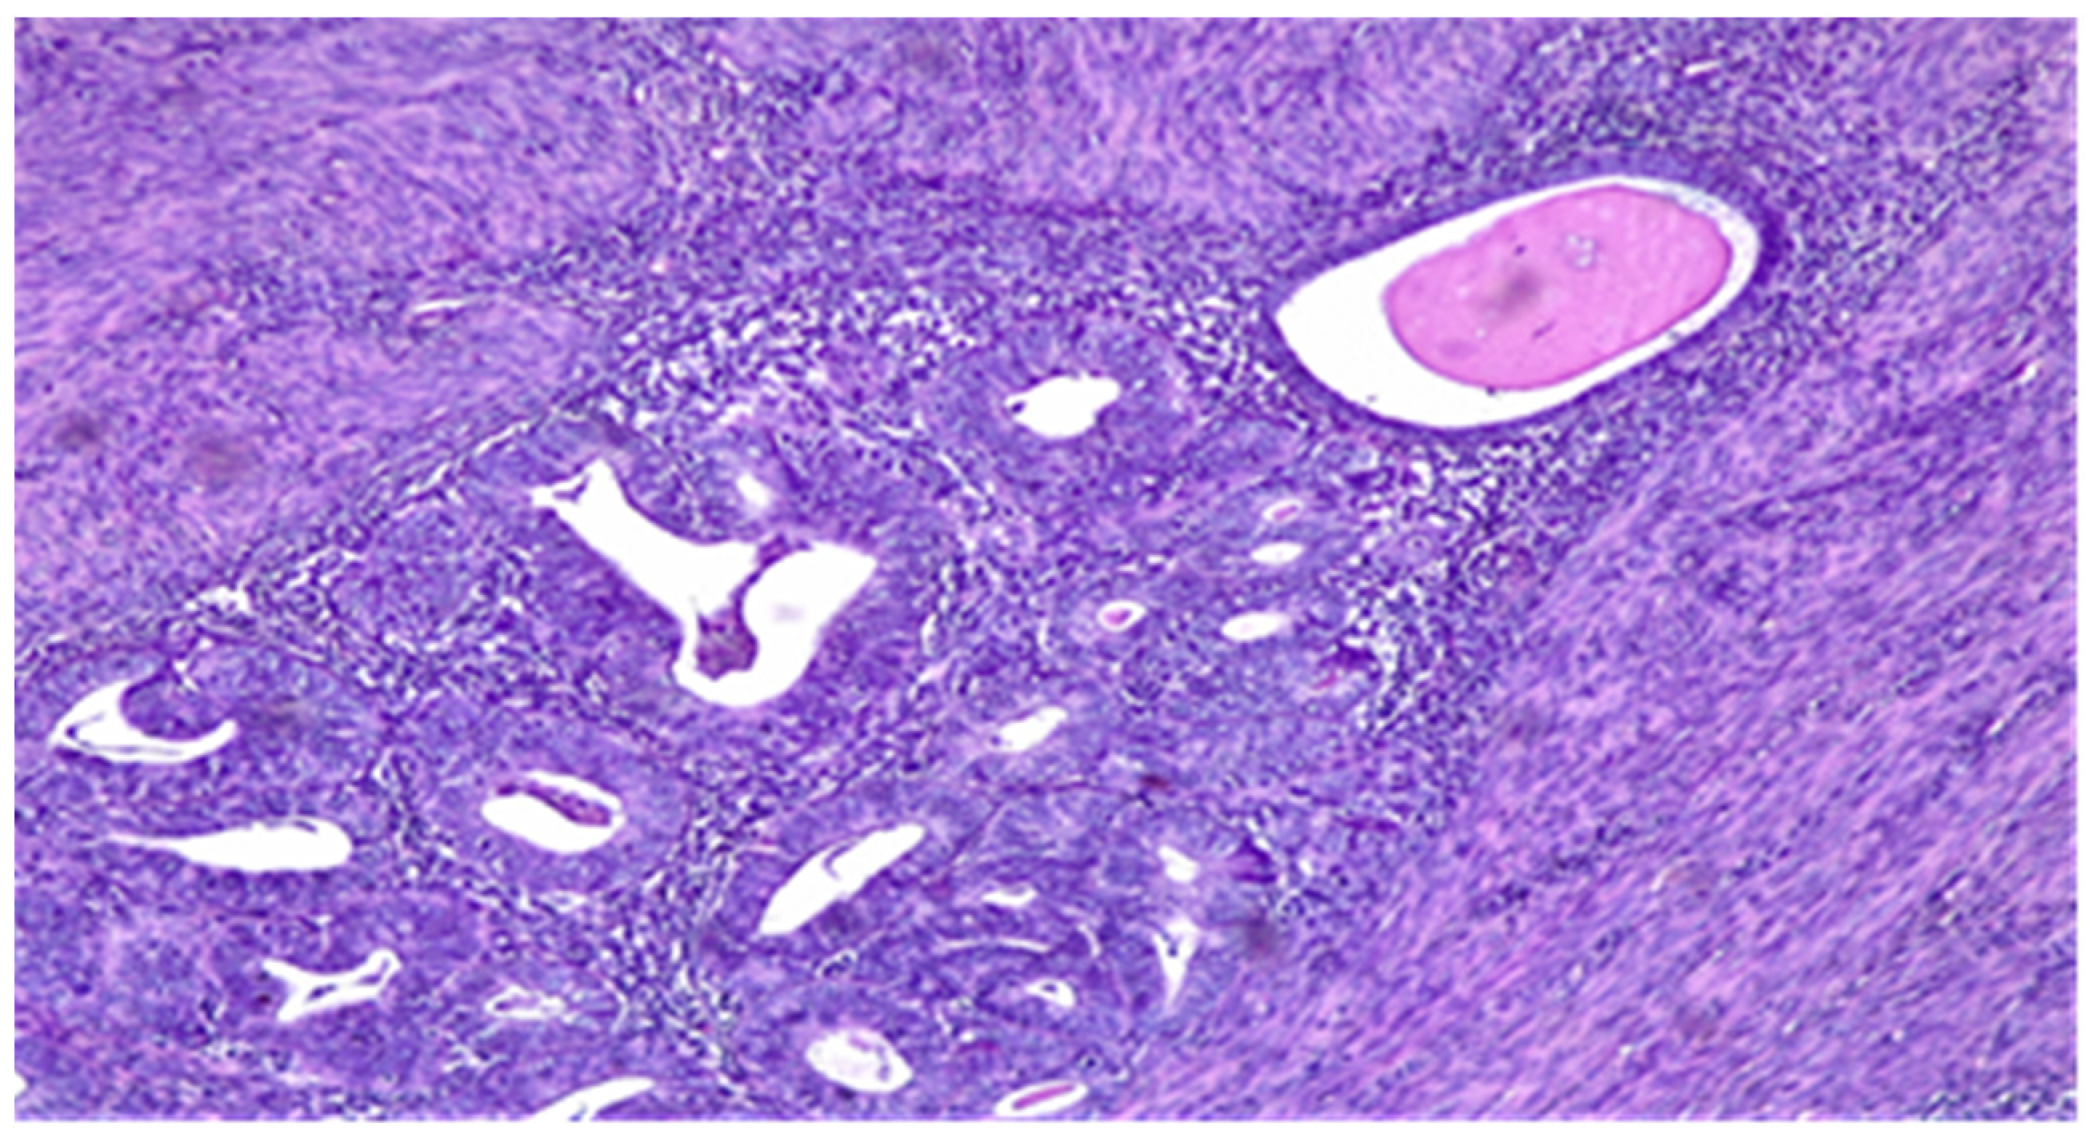

- Microcysts, lined with cells with abundant eosinophilic cytoplasm and vaguely squamoid appearance, or with flattened cells. Lumens often contain neutrophils and occasionally eosinophils.

- Elongated structures lined with the same types of cells and containing the same inflammatory cells in their lumens.

- Clusters of detached cells or individual cells lying in edematous or myxoid tissue.